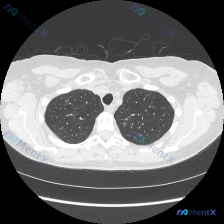

整理了一份胸部CT肺窗病例的分析思路,先看影像特征:这是胸部中上段肺窗横断面,显示右肺(图像左侧)上叶后段及下叶背段多发、散在的小结节影及条索状影,密度不均匀,部分边缘模糊,呈簇状分布,伴有小的支气管管壁增厚及管腔轻微扩张,病变沿支气管走行,符合支气管播散的特征;左肺(图像右侧)未见明显异常,双肺透...